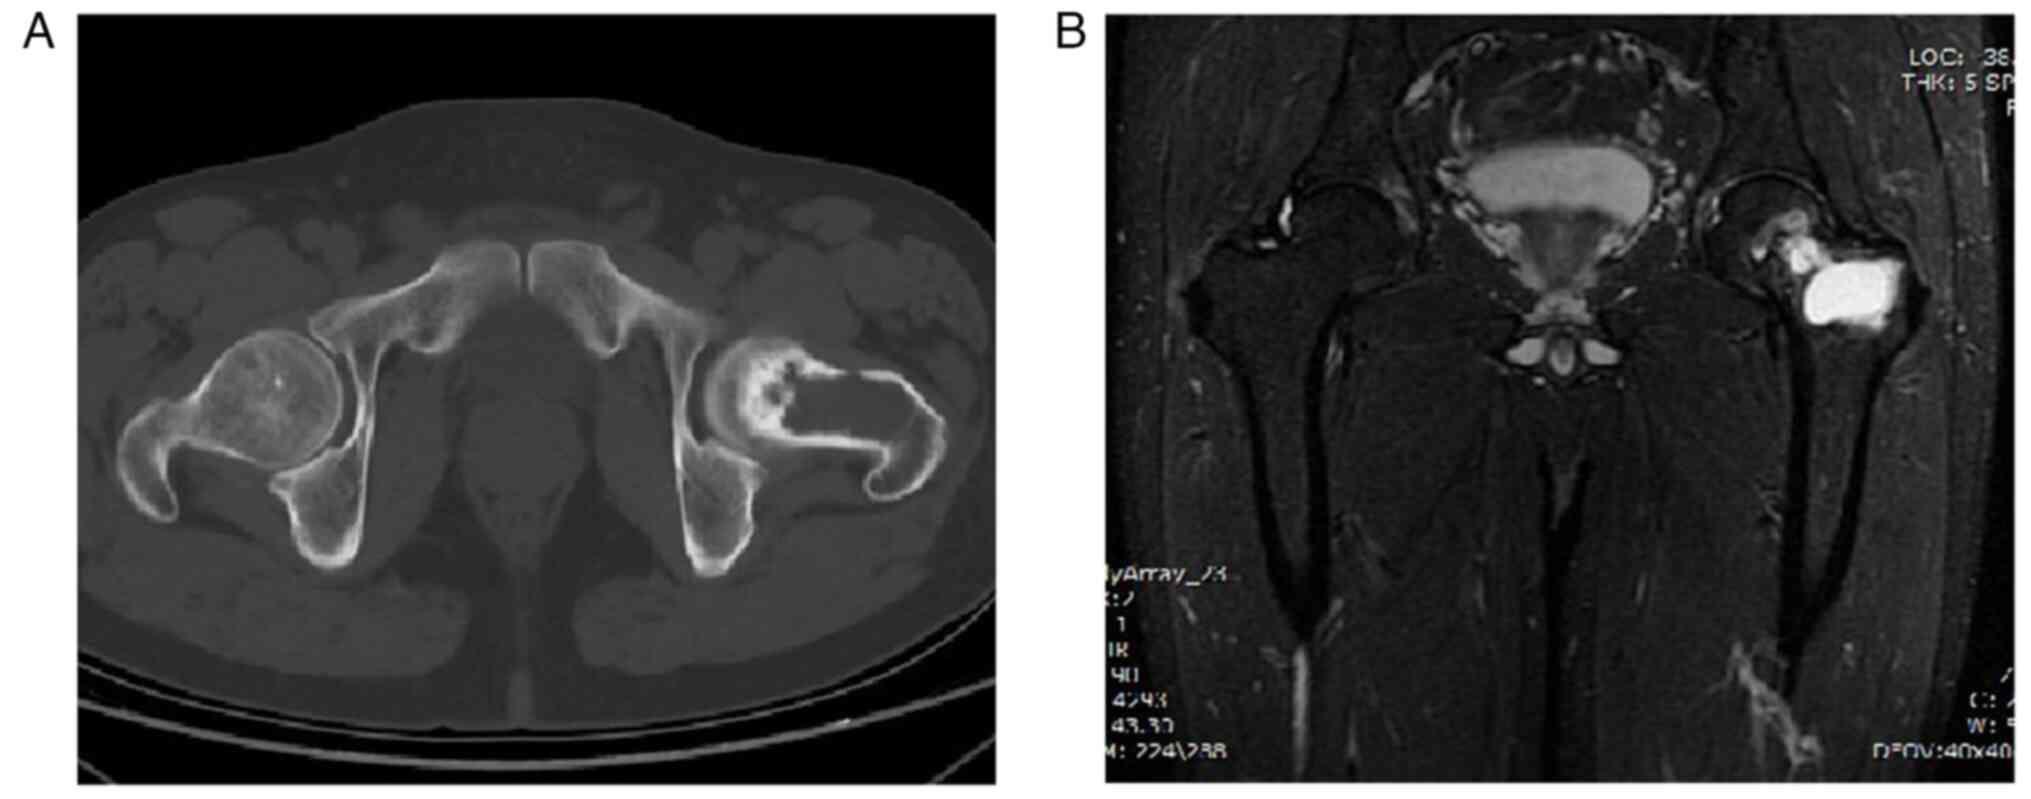

Malignant transformation of an aneurysmal bone cyst of the femoral neck: A case report

Aneurysmal bone cyst (ABC) is a benign, distending, osteolytic and locally aggressive bone tumor that is mostly associated with trauma. Approximately 1% of bone tumors are ABCs, which are most prevalent in adolescents and are usually detected in the spine and long tubular bones. The diagnosis of ABC mainly relies on histopathology, malignant transformation is rare, and the chance of malignancy increases if there are multiple recurrences. Due to the rarity of reports of malignant transformation of ABCs into osteosarcoma, there is still considerable debate on the appropriate treatment strategy. The current paper presents a case of aneurysmal bone cyst malignant to osteosarcoma and the therapeutic measures to provide expertise for the diagnosis and treatment of ABCs that are malignant to osteosarcoma.